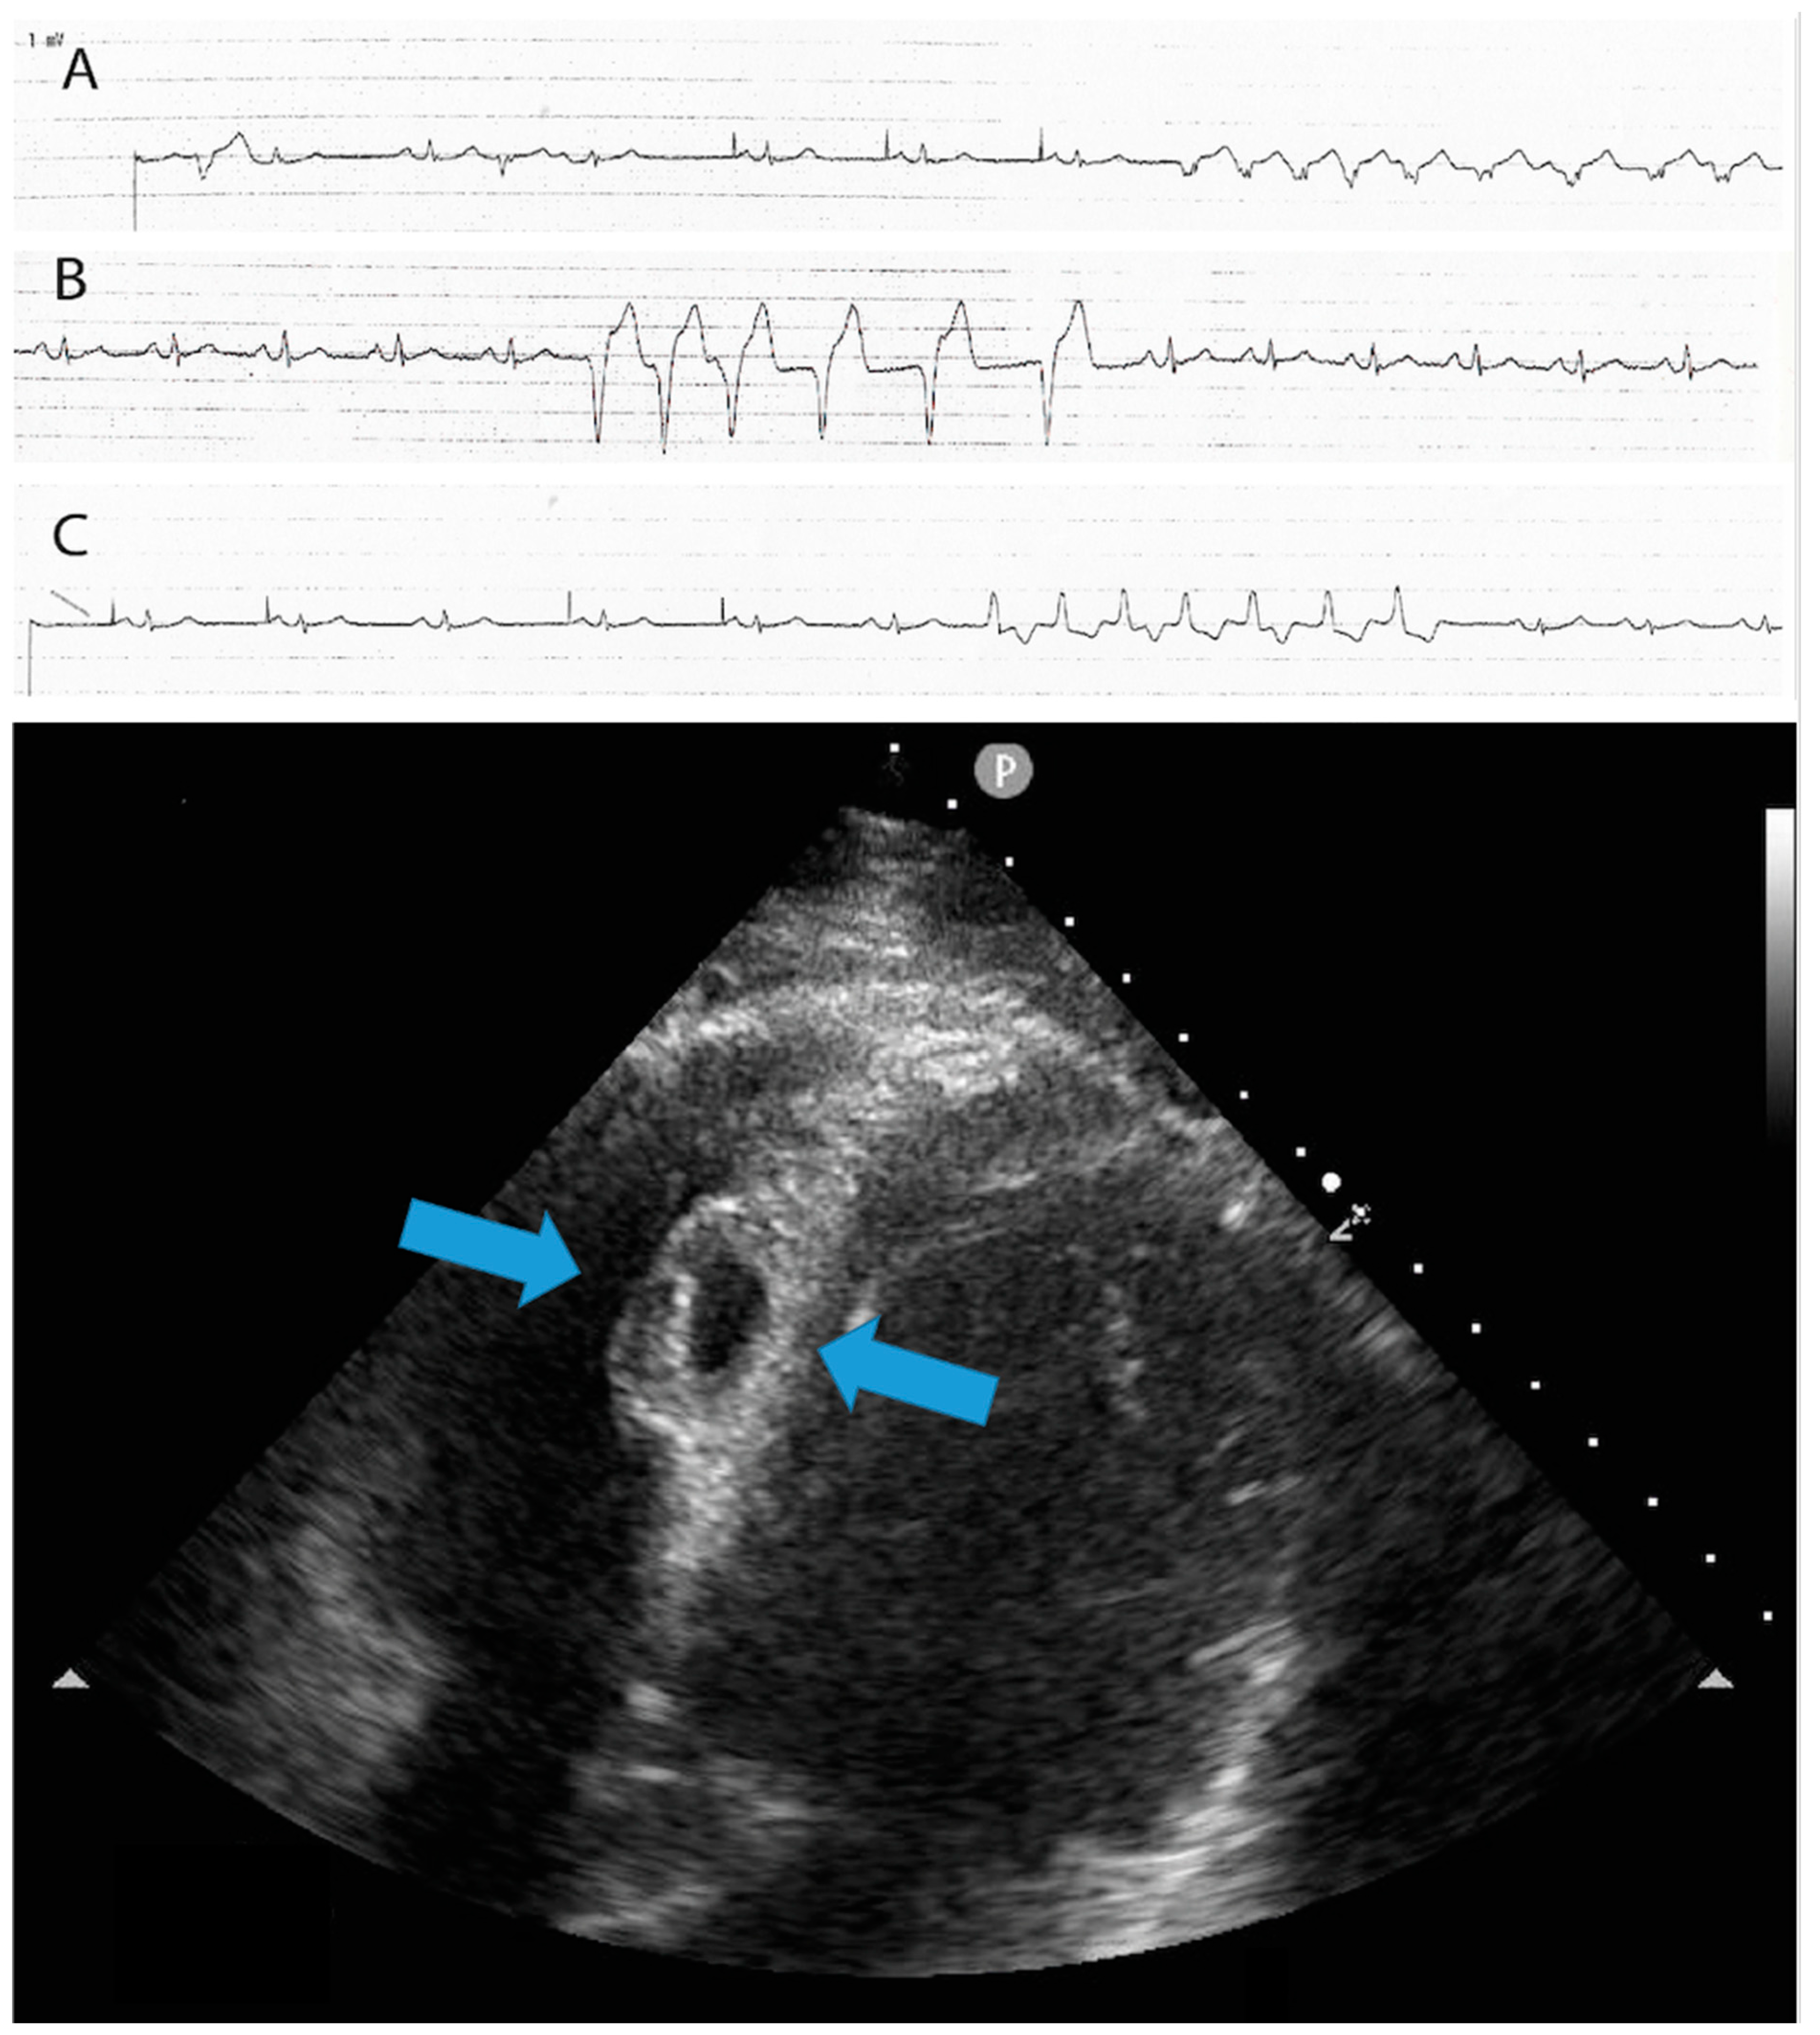

Figure 3.

The upper part of the image shows the presence of non-sustained ventricular tachycardia (NSVT) and ventricular ectopic beats of different morphologies, which developed at the end of the procedure and persisted the following day. The lower part of the image displays a 4-chamber view echocardiogram conducted the day after the procedure. It reveals the presence of an interventricular septal hematoma measuring 17 × 10 mm, which protruded into the right ventricle (RV)—light blue arrows. A, B and C strips shows non-sustained ventricular tachycardia with different morphologies.